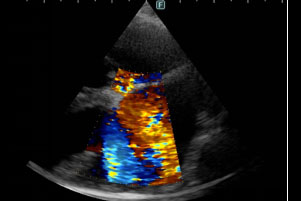

次に雑音の原因や心臓の機能を確認するため、心臓の超音波検査を実施しました。

左心房と左心室の間にある僧帽弁から、重度に逆流所見が確認できました。(図2参照)

ワンちゃんで多い僧帽弁閉鎖不全症(弁膜症)であることがわかりました。

また、心臓の拡大も同時に確認されました。(図3参照)

図2

図3